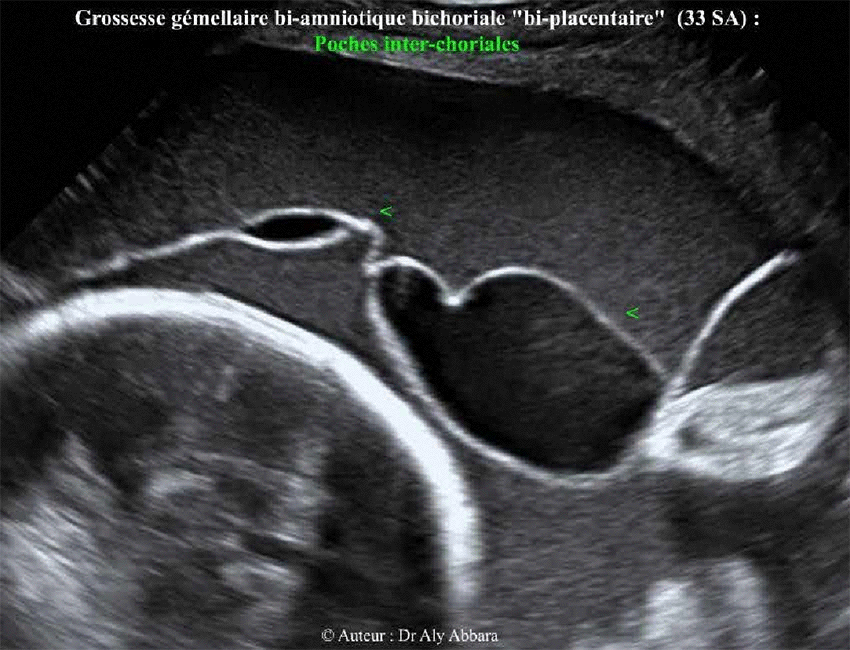

Grossesse gémellaire bi-amniotique bi-choriale (biplacentaire) - Poches interchoriales

Poches inter-choriales

• Images échographiques réalisées à 33 SA montrant la présence de multiples plages à contenu liquidien (anéchogène) situées dans l'espace inter-chorial (entre les deux chorions) de la cloison qui sépare les deux cavités amniotiques de cette grossesse gémellaire bi-amniotique, bichoriale.